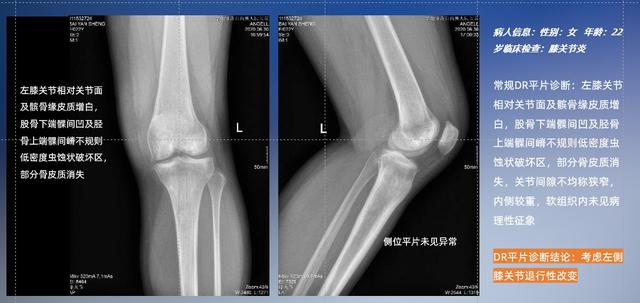

以膝关节疾病检查为例,膝关节在解剖学意义上是一种较为复杂的最大关节,由胫骨上端、股骨下端及髌骨组成。在股骨与胫骨的关节面之间存在两块半月板,分别处于内侧、外侧。膝关节的运动主要为伸、屈,在半屈位时可进行小幅度的旋外、旋内运动。随着现代人们体育生活以及肥胖的增加,膝关节疾病出现高发趋势,特别是关节磨损、膝关节炎与骨关节炎等关节退行性改变,长时间的内翻负荷会造成内侧关节软骨、骨性关节面的磨损。目前针对此类疾病的检查主要为平片下的负重位检查、CT检查以及MRI检查,相较于非负重位检查,负重位检查能更加真实反映膝关节结构中胫骨、股骨、髌骨实际对位关系和关节面的形态特征及关节间隙大小,对膝关节骨关节病诊断准确率高。

普通平片扫描与WR-3D扫描前后诊断结果对比

与此同时,数字化X线摄影技术相较于CTMRI来说,能快速获取真实、直观、满足临床需要的影像。DR的图像具有图像层次丰富、空间分辨力高、影像边缘锐利清晰、密度分辨力高级细微结构表现出色等特点,针对膝关节解剖结构数字化X线摄影技术应用价值很高,尤其是是对骨小梁与骨皮质的显示非常清楚。在负重位状态下,数字化X线三维摄影扫描与重建,能够更好的呈现受检者关节受力改变的状态。太阳成集团tyc122cc入口科技创新的WR-3D动态三维数字化X线摄影技术,通过数字化X线摄影完成三维扫描并重建三维影像信息,包括MPR多平面重建、MIP重建以及VR绘制。扫描时间短,剂量相较于CT设备大幅缩减,同时成本更低,在临床诊断以及医疗方案制定中具有极大的价值意义。相较于普通平片下的负重位扫描,负重位动态三维扫描摄影技术能够避免二维状态下的组织结构重叠、密度分辨率不足、组织解剖结构难以分辨等问题,WR-3D支持多角度的动态三维摄影观察,能全面的呈现被检查部位在多个角度下三维影像信息,极大的减少了二维负重位检查的漏诊率。